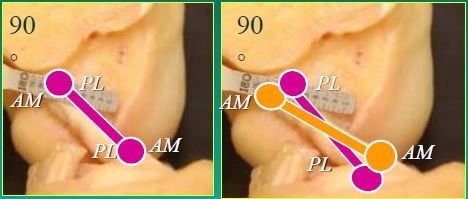

–Διπλή δεσμίδα, όπως και είναι η πραγματική σύνθεση του συνδέσμου αντί για την κλασική μονή δεσμίδα (εικόνα 1). Με τον τρόπο αυτόν προσφέρεται επιπλέον στροφική σταθερότητα. Για πρώτη φορά έγινε στην Ελλάδα από τον Ορθοπαιδικό μας Δρα Δημοσθένη Αλασεϊρλή, ο οποίος διατηρεί και την μοναδική σειρά ασθενών στην χώρα μας.